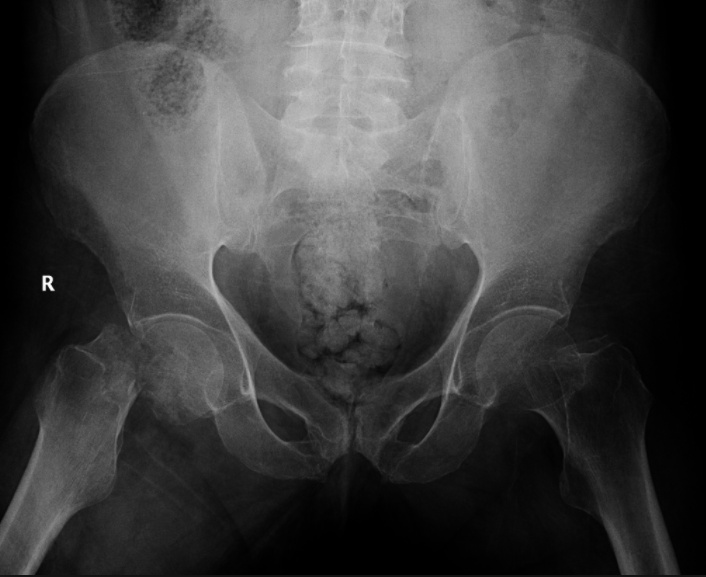

Pelvic

Pelvic fracture generally refers to a fracture of the acetabulum that occurs due to high-energy trauma in younger patients or a fall in older patients.

Patients with a pelvic fracture are unable to bear weight and may have a malrotated lower extremity.

A patient with major pelvic trauma who is hemodynamically unstable should receive a focused assessment with sonography for trauma (FAST).

If positive, the patient should be taken to the OR to address abdominal hemorrhage. Pelvic arteriography can be used if needed.

If negative, the patient should receive a diagnostic peritoneal aspirate. If positive, treat like positive FAST. If negative, extraabdominal hemorrhage should be controlled with pelvic stabilization and preperitoneal packing or pelvic arteriography.

A patient with major pelvic trauma who is hemodynamically stable should receive an abdominal CT scan.

If there are signs of active pelvic bleeding, pelvic arteriography should be performed. If there are no signs of active pelvic bleeding, the patient should be observed with serial examination.